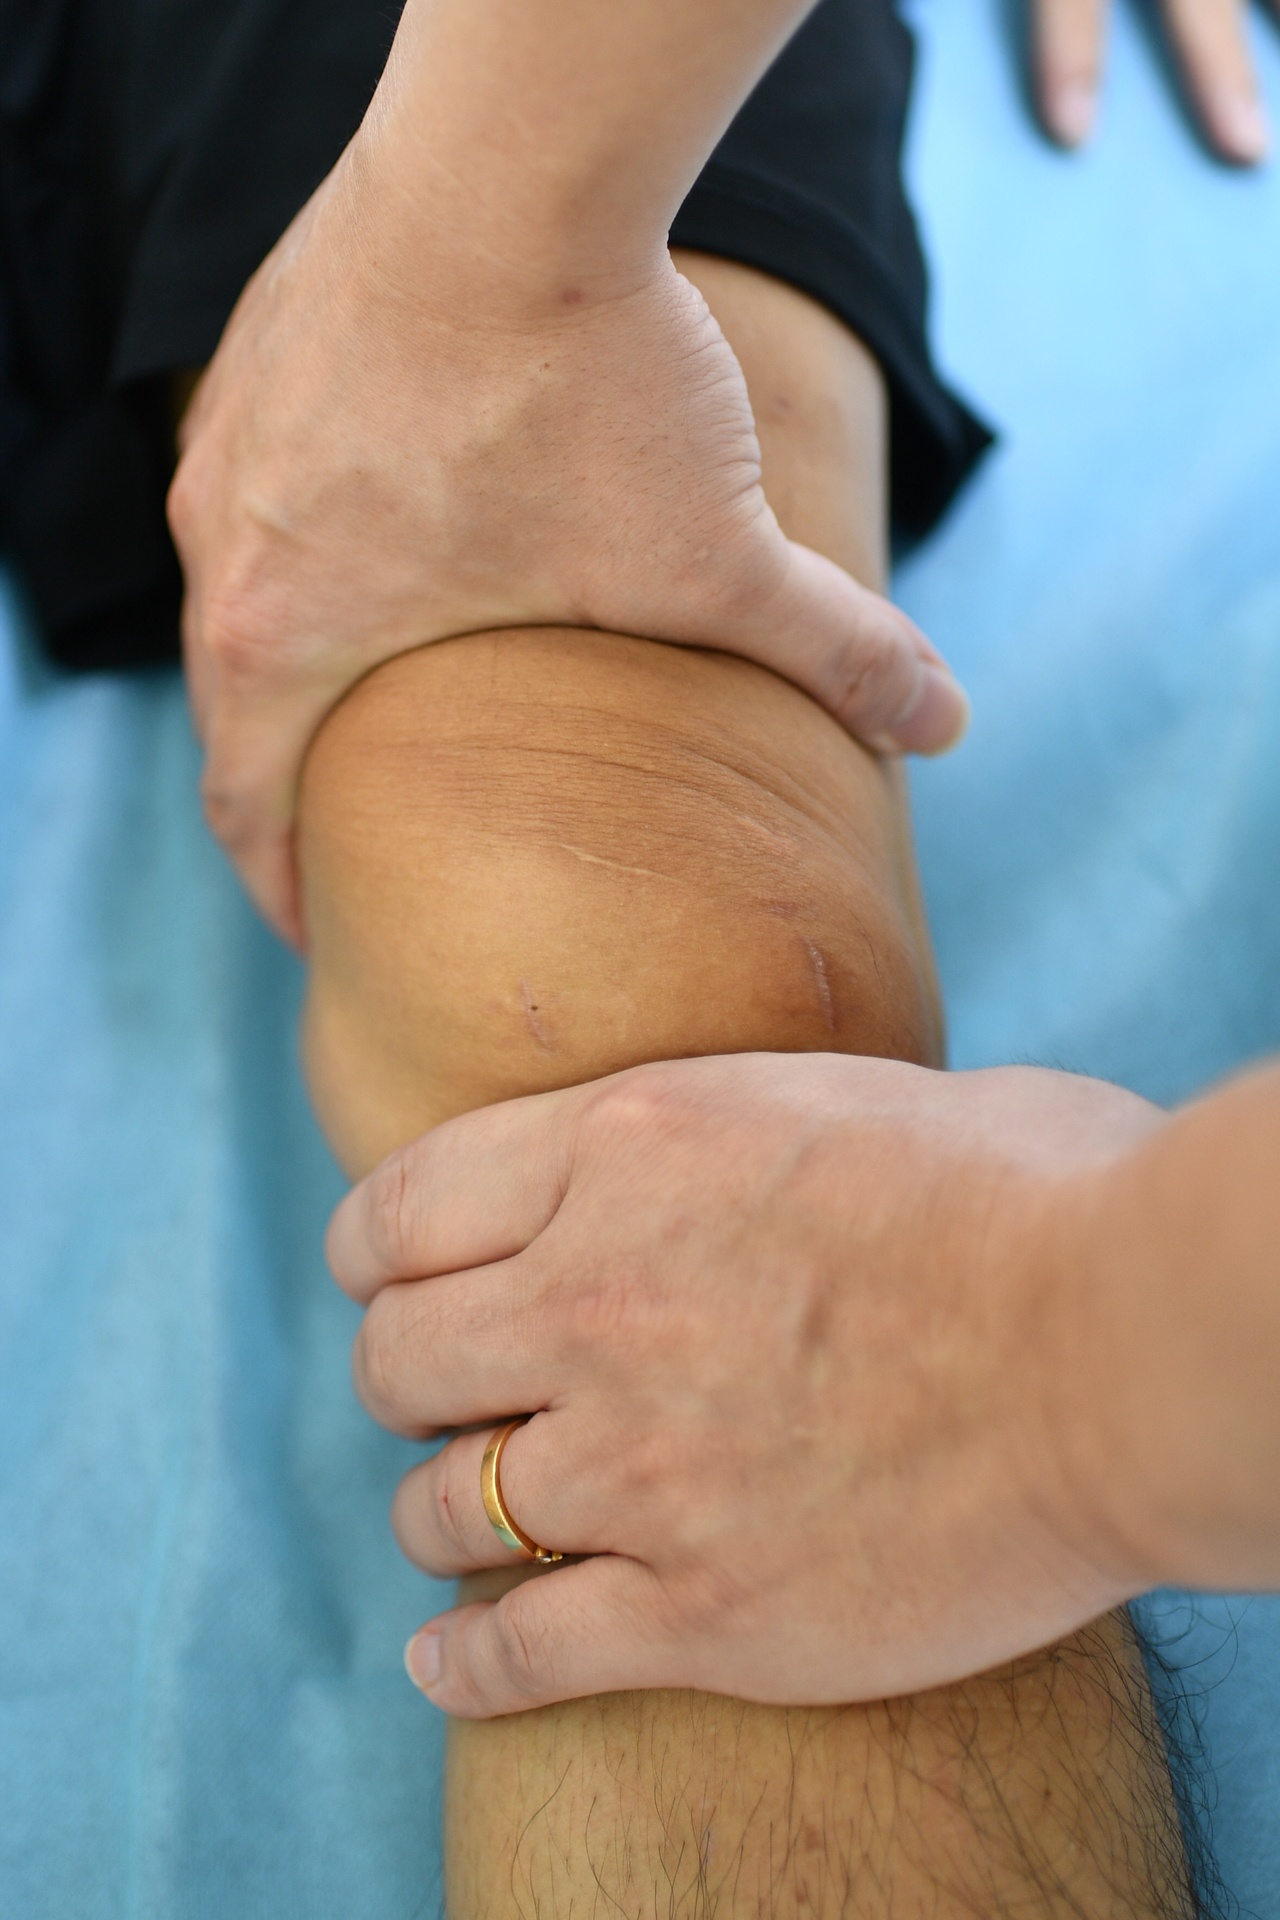

| Vợ đưa tôi đến Trung tâm Chấn thương chỉnh hình - BVĐK Tâm Anh TP.HCM để khám và chụp chiếu vì ở đây có tiếng về điều trị chấn thương thể thao, lại có máy móc chụp chiếu hiện đại. Bác sĩ Trần Anh Vũ (Trưởng khoa Y học thể thao - Phó giám đốc Trung tâm) thăm khám và kết luận chấn thương cho tôi từ ngày đầu, cũng là người trực tiếp thực hiện ca phẫu thuật. Trước ngày mổ, anh thường qua phòng bệnh trò chuyện với tôi. Sự ân cần của anh cũng như các điều dưỡng khiến tôi cảm thấy yên tâm hơn nhiều. |